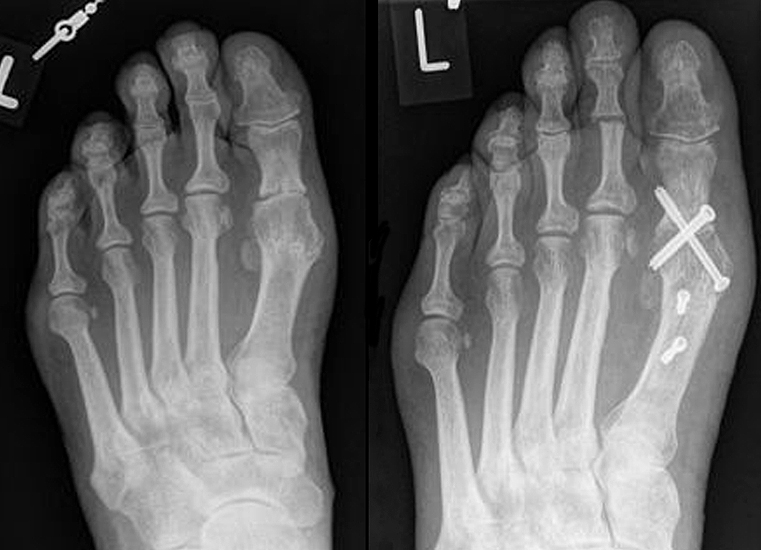

Die Röntgenaufnahmen (Abbildung 1) zeigen den Fuß einer 34 jährigen Patientin nach Exostosenabtragung. Der erhöhte intermetatarsale Winkel wurde durch eine alleinige Abtragung der Exostose nicht reduziert. Als weiterer Risikofaktor für ein Rezidiv liegt ein pathologischer Gelenkwinkel vor. Der intermetatarsale Winkel von 18 Grad kann durch eine basisnahe Osteotomie gut korrigiert werden. Da durch die gleichzeitige distale Korrektur des Gelenkflächenwinkels mithilfe einer Reverden-Green Osteotomie ein Längenverlust von ca. 2-4 mm einhergeht, bot sich als proximales Korrekturverfahren die basisnahe Open-wedge Osteotomie an, um bezüglich der Länge des Metatarsale I neutral zu bleiben (Abbildung 2). Die Kombination zweier verkürzender Verfahren (z.B. Lapidus und Reverden-Green) würden zu einem sehr kurzen ersten Strahl führen, mit dem Risiko einer Transfermetatarsalgie. Übersteigt die Verkürzung des Metatarsale I 2 mm, steigt das Risiko für die Entwicklung einer Transfermetatarsalgie deutlich an 8. Die durchgeführte Revision zeigt eine gute Stellung des 1. Strahls bei zentriert stehendem Gelenk.